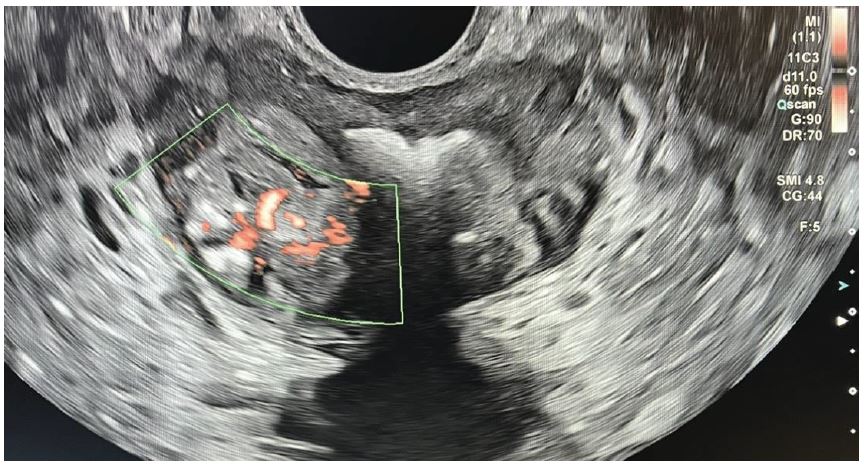

Значення ПСА вище вказаних значень до 10 нг/мл прийнято позначати «сірою зоною», коли важко визначити показання до проведення біопсії ПЗ. Значення ПСА вище 10 нг/мл є основою проведення біопсії ПЗ. Хворому була виконана трансректальна поліфокальна біопсія ПЗ під мультипараметричною (мп) ультразвуковою навігацією та ехоконтрастуванням Соновью (рис. 1 - 5).

Рис. 2. Кольорова доплерографія. Аксіальне зображення.